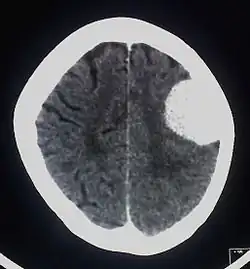

Meningeoom

Een meningeoom is een meestal goedaardige tumor, uitgaande van de hersenvliezen (arachnoidea). Ze groeien langzaam en verdringen het zenuwweefsel. Ze geven meestal weinig klachten tot de normale anatomie van de hersenen zo sterk is vervormd dat er functiestoornissen ontstaan. Het kan dan bijvoorbeeld gaan om focale epileptische aanvallen, of om paresen. Wanneer het meningeoom zich echter nestelt aan het diafragma sellae bij de hypofyse, kunnen oogklachten ontstaan. Doordat de tumor de oogzenuw verdrukt kan één of beide oogzenuwen beschadigd raken. Door de witte verkleuring op scans kan ten onrechte gedacht worden aan een hypofysetumor of beginnende MS.